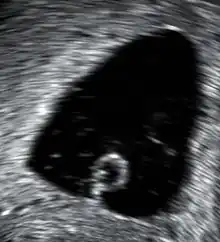

![]() | |

| An ultrasound showing a gestational sac containing a yolk sac but no embryo | |